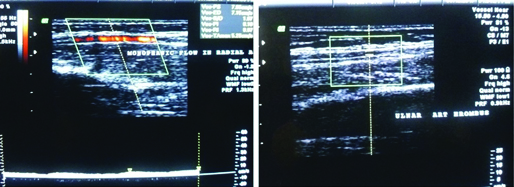

After 10 days of enucleation, the patient presented with multiple episodes of convulsions and vomiting which were not associated with fever. Cardio-respiratory and neurological examination were normal. The peripheral pulses in all limbs were equally palpable. Clinically suspecting increased intracranial pressure patient started treatment empirically with mannitol and phenytoin. Patient improved symptomatically within 48 hours of admission and on day 3 of admission, the patient developed pain and bluish discolouration of the digits of the left hand [Table/Fig-3,4]. The left hand was less warm than the right. The left radial pulse was not palpable. The child did not have a history suggestive of collagen vascular disease or Raynaud’s phenomenon in the past. Color Doppler showed occlusion of radial and ulnar arteries of the left limb [Table/Fig-5].

Occlusion of radial and ulnar arteries of the left limb.